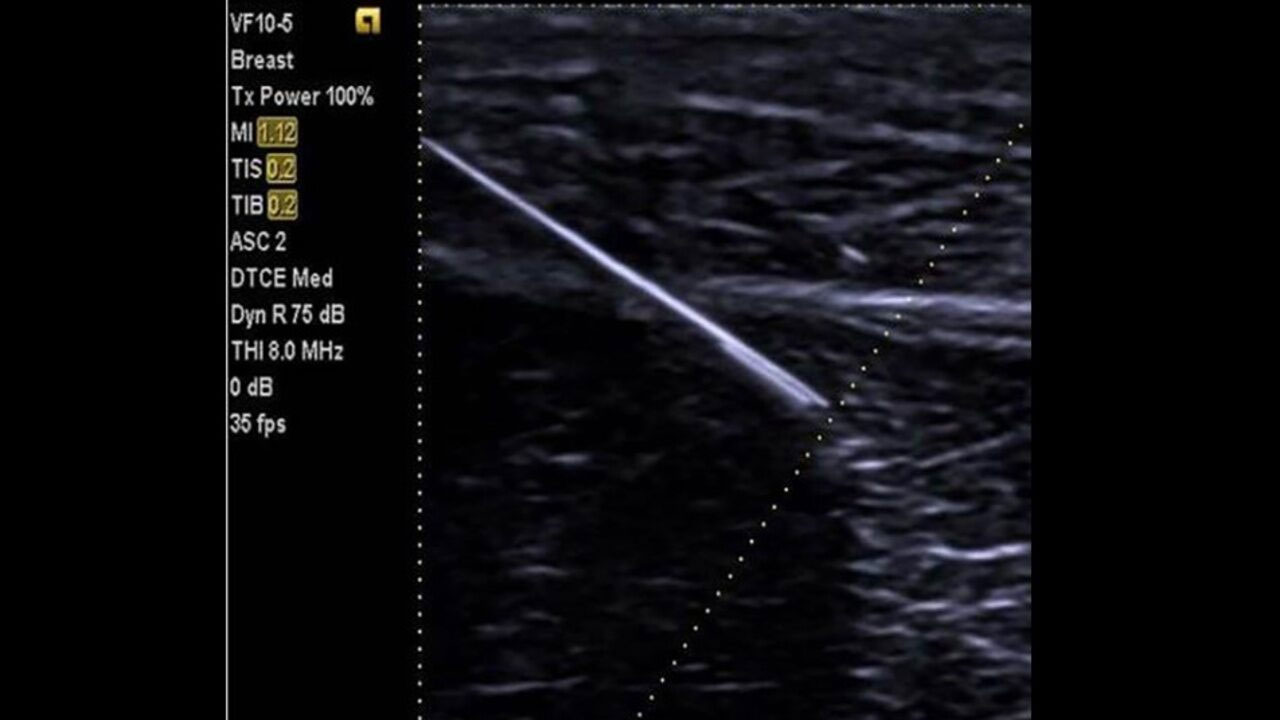

- Новая технология улучшенной визуализации биопсийной иглы (Needle Visualization Enhancement) использует ультразвуковой компаундинг - многолучевое составное сканирование, при этом сохраняя отличное качество ультразвукового изображения, особенно под более острыми углами прохождения биопсийной иглы

Технология улучшенной визуализации позволяет усиливать ЭХО-сигнал от биопсийной иглы при формировании изображения во время инвазивных манипуляций. Использование инновационных технологий формирования изображения иглы при различных углах введения иглы позволяет получать четкие УЗ-срезы без уменьшения частоты кадров. |